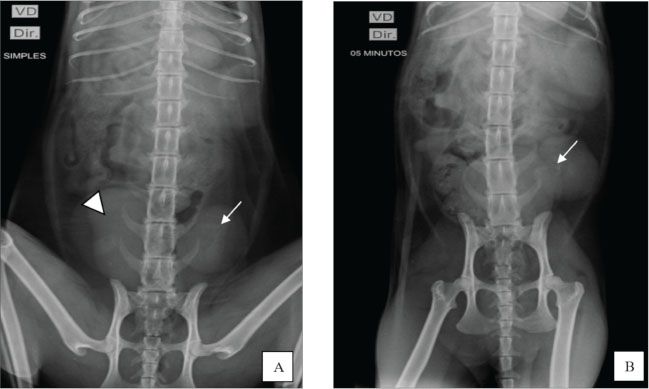

Before contrast media administration, plain abdominal radiographs were performed in ventrodorsal (VD), oblique (the X-ray entered the body through the right ventrolateral side and exited through ventrolateral on the left side), and right lateral projections. All projections showed the absence of the right renal silhouette, while the left kidney was located in the caudal portion of the abdominal cavity, presenting slightly lobulated contours and measuring 3.96 cm in length (Fig. 2A).

Fig. 2. Excretory urography. A) Ventrodorsal plain radiography revealed no visualization of the right renal silhouette, whereas the left kidney (arrow) was identified in the caudal portion of the abdominal cavity, next to the bladder (arrowhead). B) Contrast-enhanced radiograph in the VD projection shows the left ureter filled with contrast (arrow) in the renal pelvis, indicating the beginning of the pyelogram. Greater opacification is noted in the left kidney, which shows signs of slight pelvic dilation.

After contrast administration, radiographs were taken in the ventrodorsal, right lateral, and oblique projections at 5, 15, and 30 minutes. At 5 minutes, the image showed the initial phase of the left nephrogram, confirming the absence of the right kidney. At the end of the evaluation, the remaining kidney showed signs of pyelectasis and renal cortical thinning (Fig. 2B).